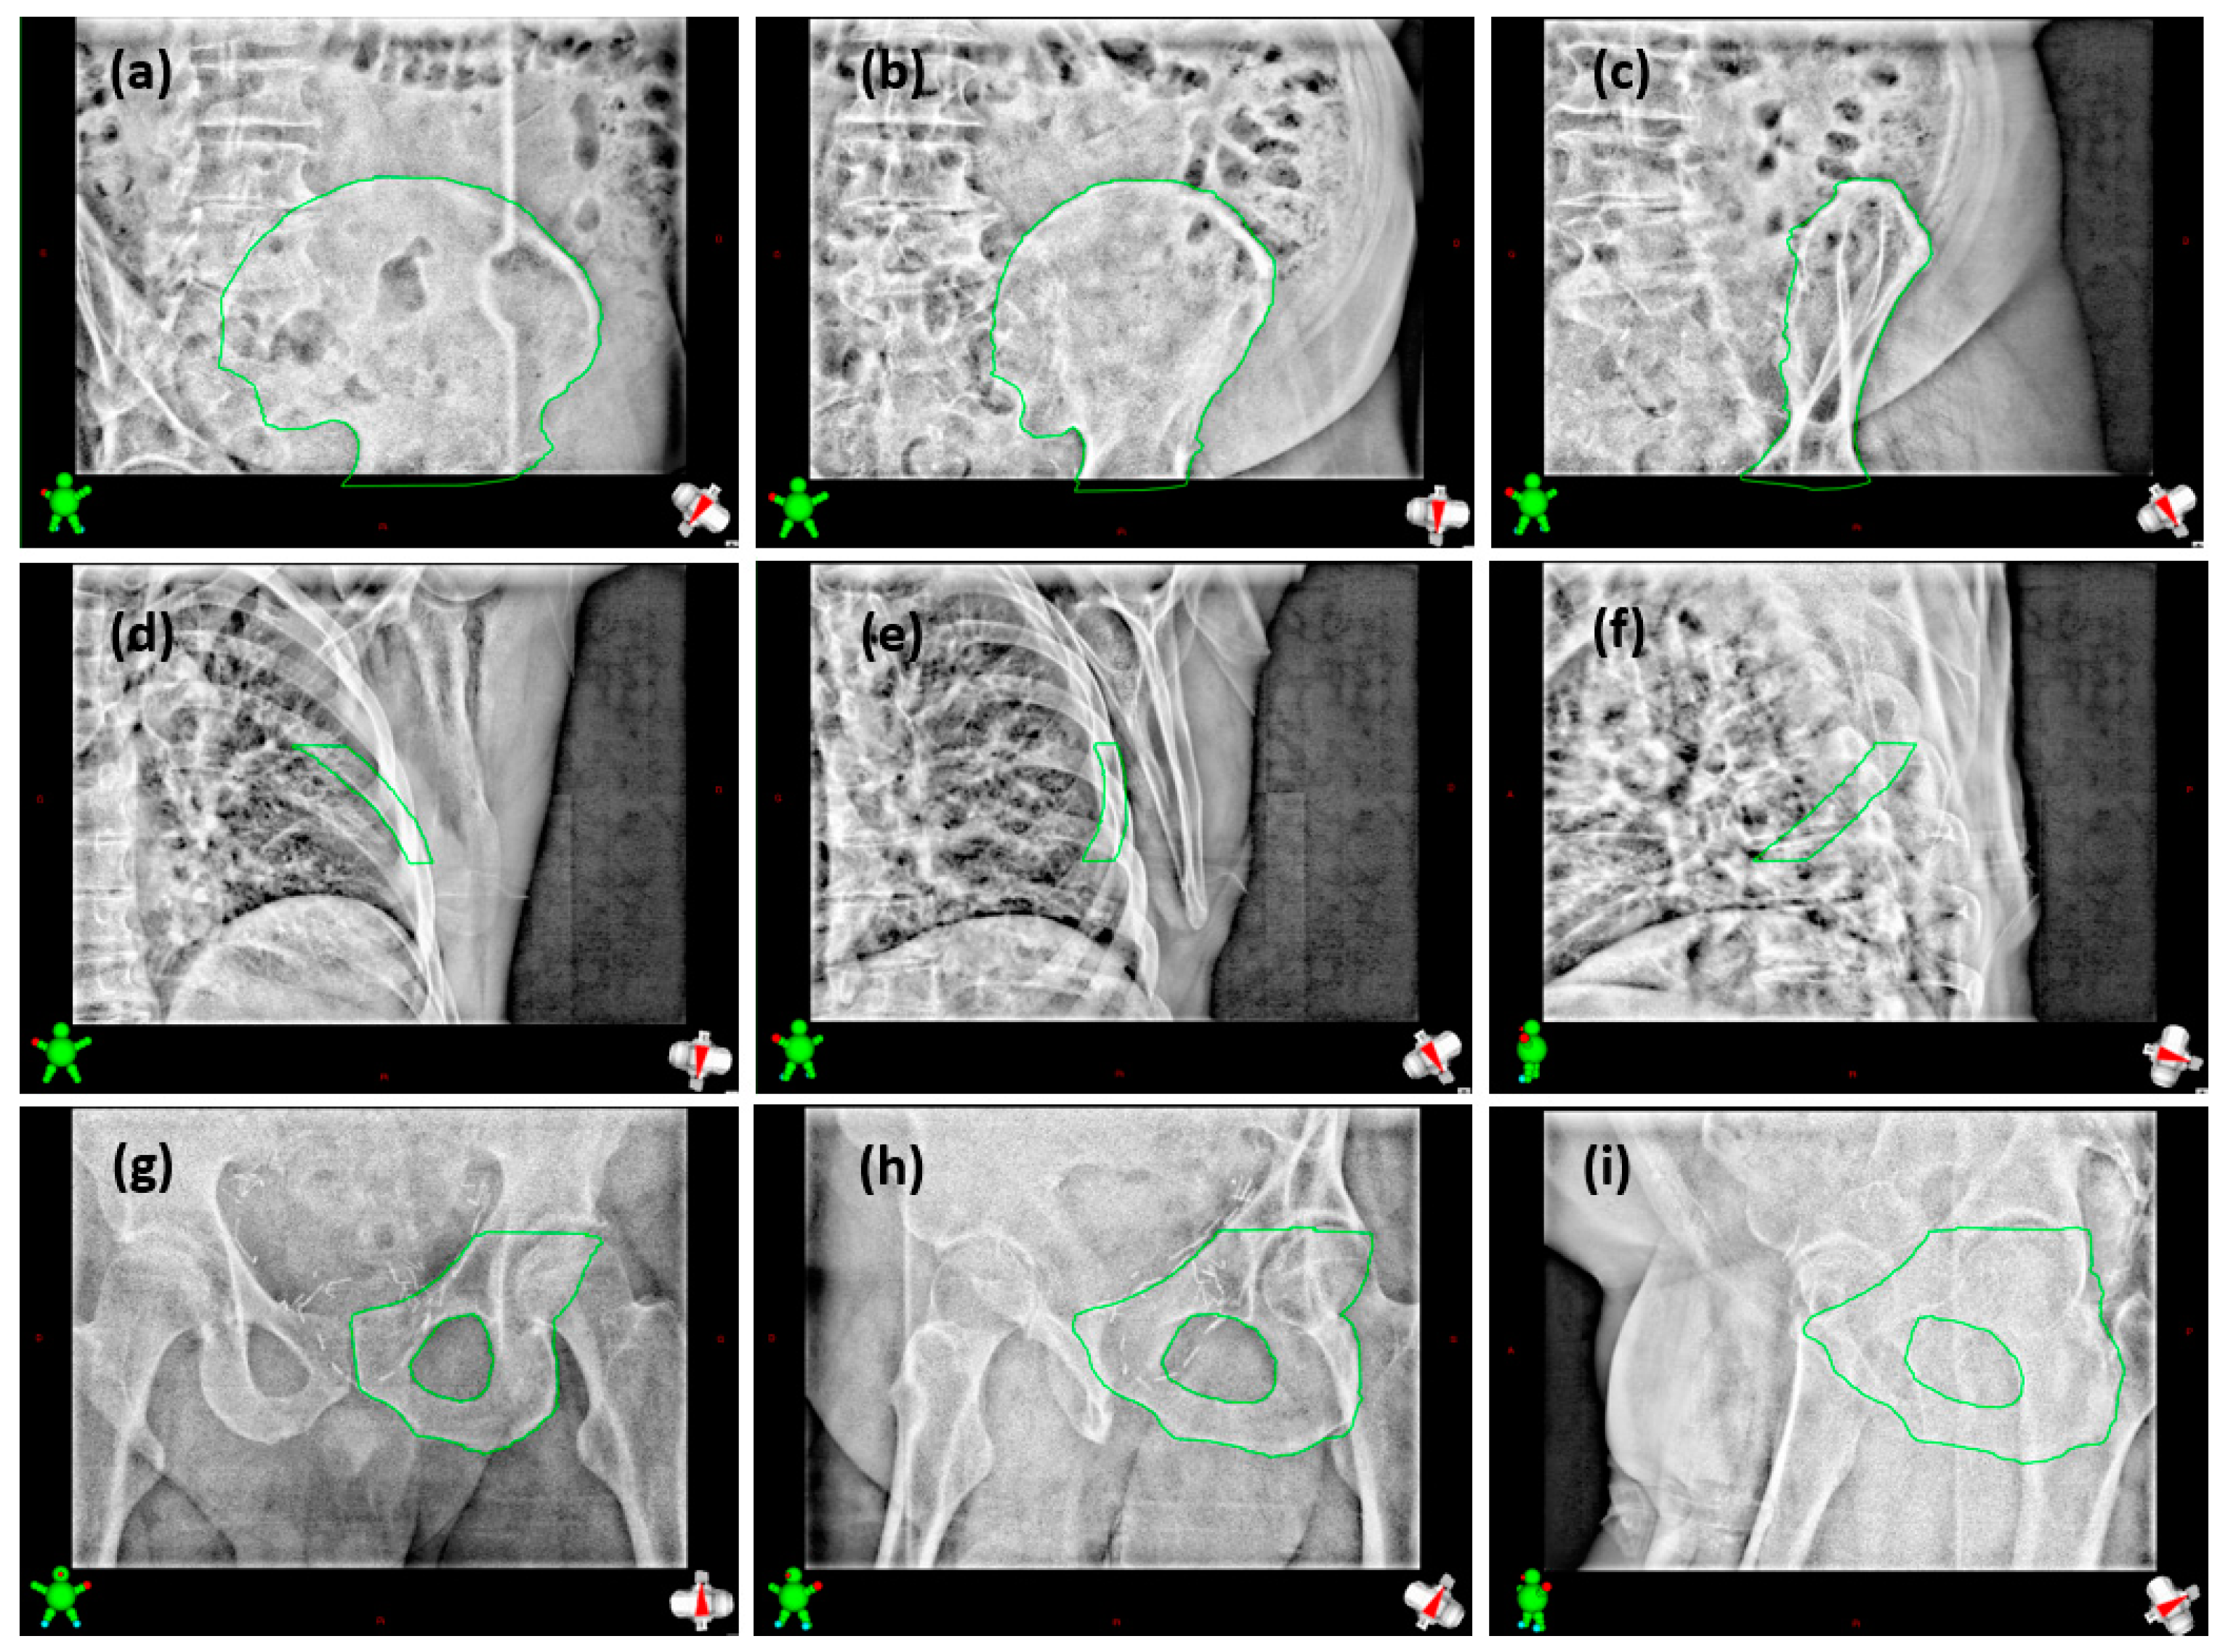

2. Materials and Methods

2.2. Patient Study

2.3. Analysis Method